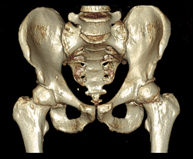

- TC Pelvis ósea Exploración radiológica que mediante un sistema de rayos X y detectores que giran alrededor del paciente, reconstruyendo las imágenes por ordenador (TC Multidetector), permite el estudio de huesos, músculos y articulaciones de la pelvis. Exploración radiológica que mediante un sistema de rayos X y detectores que giran alrededor del paciente, reconstruyendo las imágenes por ordenador (TC Multidetector), permite el estudio de huesos, músculos y articulaciones de la pelvis.

- TC Caderas Exploración radiológica que mediante un sistema de rayos X y detectores que giran alrededor del paciente, reconstruyendo las imágenes por ordenador (TC Multidetector), permite el estudio de huesos, músculos y articulaciones de la cadera. Exploración radiológica que mediante un sistema de rayos X y detectores que giran alrededor del paciente, reconstruyendo las imágenes por ordenador (TC Multidetector), permite el estudio de huesos, músculos y articulaciones de la cadera.

- TC Pelvis Prueba diagnóstica que consiste en obtener imágenes bi y tridimensionales de la pelvis de alta definición anatómica (estructuras óseas, estructuras vasculares, vejiga, útero y ovarios, próstata y vesículas seminales, uréteres, etc.) mediante el empleo de un equipo de TC (Tomografía Computarizada). La mayoría de estudios requieren el empleo de contraste yodado. Prueba diagnóstica que consiste en obtener imágenes bi y tridimensionales de la pelvis de alta definición anatómica (estructuras óseas, estructuras vasculares, vejiga, útero y ovarios, próstata y vesículas seminales, uréteres, etc.) mediante el empleo de un equipo de TC (Tomografía Computarizada). La mayoría de estudios requieren el empleo de contraste yodado.